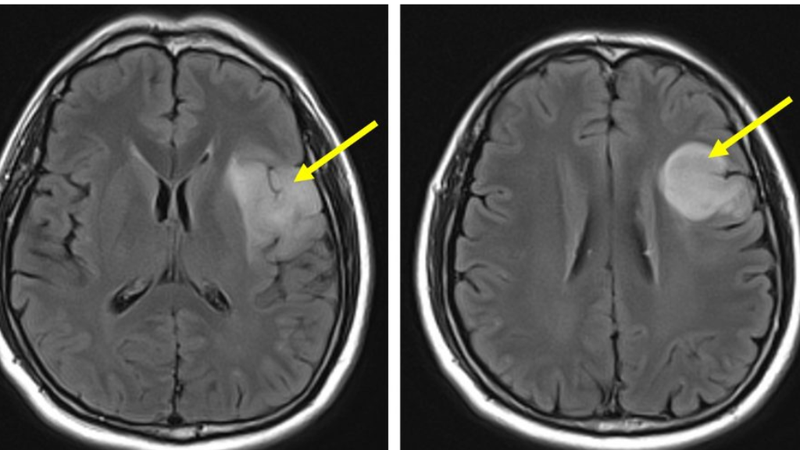

Chẩn đoán u thần kinh đệm bậc thấp thường bao gồm sử dụng các phương pháp hình ảnh học: